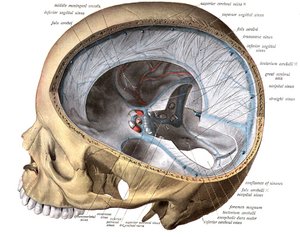

Dural venous sinuses bordered by hard meninges (shown in blue) direct blood outflow from cerebral veins to the internal jugular vein at the base of skull

The veins of the brain, both the superficial veins and the deep venous system, empty into the dural venous sinuses, which carry blood back to the jugular vein and thence to the heart. In cerebral venous thrombosis, blood clots usually form both in the veins of the brain and the venous sinuses. The thrombosis of the veins themselves causes venous infarction (damage to brain tissue due to a congested and therefore insufficient blood supply). This results in cerebral edema (both vasogenic and cytotoxic edema), and leads to small petechial haemorrhages that may merge into large haematomas. Thrombosis of the sinuses is the main mechanism behind the increase in intracranial pressure due to decreased resorption of cerebrospinal fluid (CSF). The condition does not typically lead to hydrocephalus, however, because there is no difference in pressure between various parts of the brain.[3] However, those who have deep cerebral venous sinus thrombosis or oedema at basal ganglia are more prone to hydrocephalus development.[13]

Any blood clot forms due to an imbalance between coagulation (the formation of the insoluble blood protein fibrin) and fibrinolysis. The three major mechanisms for such an imbalance are enumerated in Virchow's triad: alterations in normal blood flow, injury to the blood vessel wall, and alterations in the constitution of blood (hypercoagulability). Most cases of cerebral venous sinus thrombosis are due to hypercoagulability.[3] The inflammatory response and prolonged immobilization of patients with COVID-19 may also help explain the formation of CVST.[14]